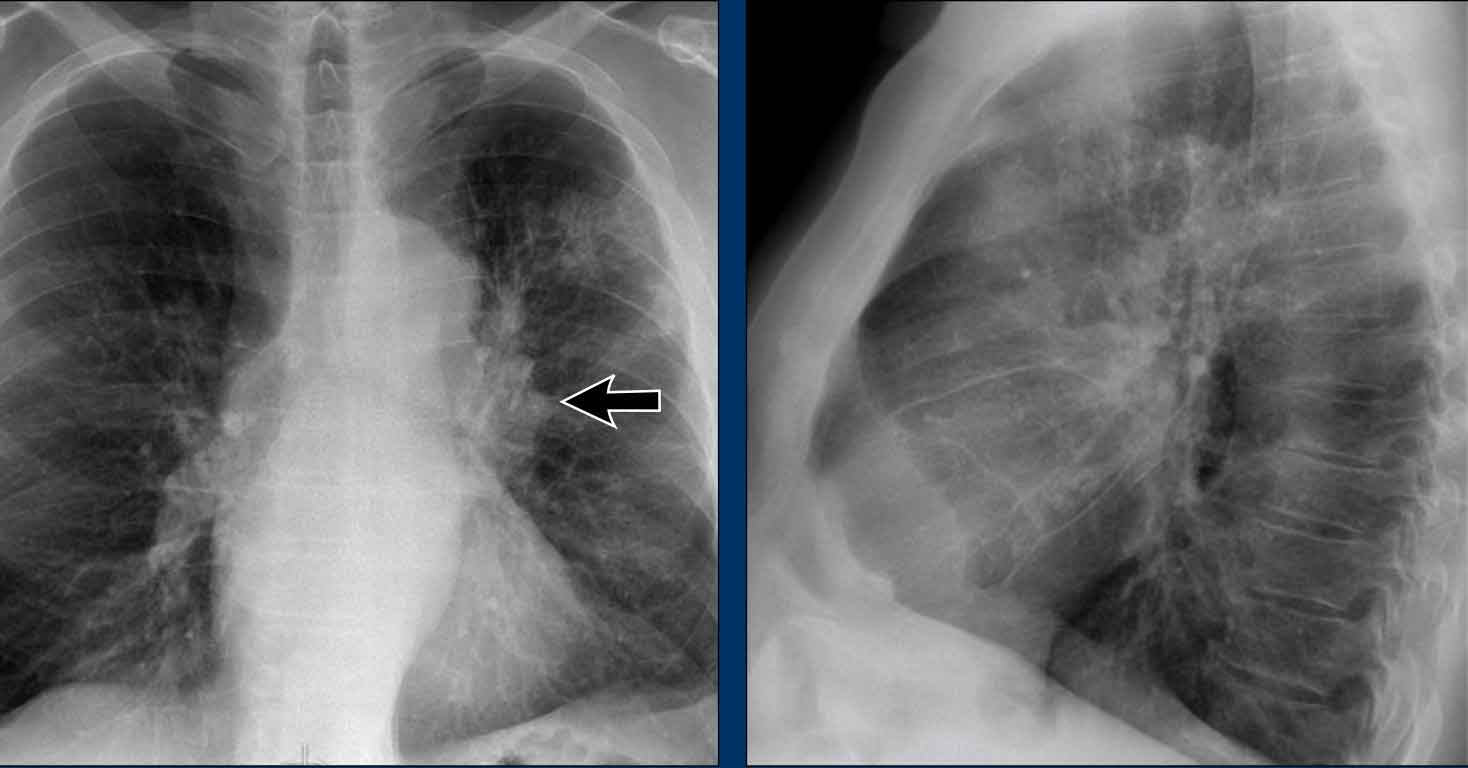

Displacement of the Azygoesophageal Line (1) – Hiatal hernia

A hiatal hernia (arrowheads) is the most common cause of displacement of the azygoesophageal line as seen on the PA-view.

Notice the air within the hernia on the lateral view (black arrow).

Displacement of the Azygoesophageal Line (2) – Subcarinal Lymphadenopathy

A common cause of displacement of the azygoesophageal line is subcarinal lymphadenopathy (station 7).

On the chest X-ray, note superior displacement of the azygoesophageal line just below the carina, consistent with enlarged subcarinal lymph nodes (black arrow).

Additional right paratracheal lymphadenopathy is seen, displacing the right paratracheal stripe (white arrow) and deviating the trachea to the left.